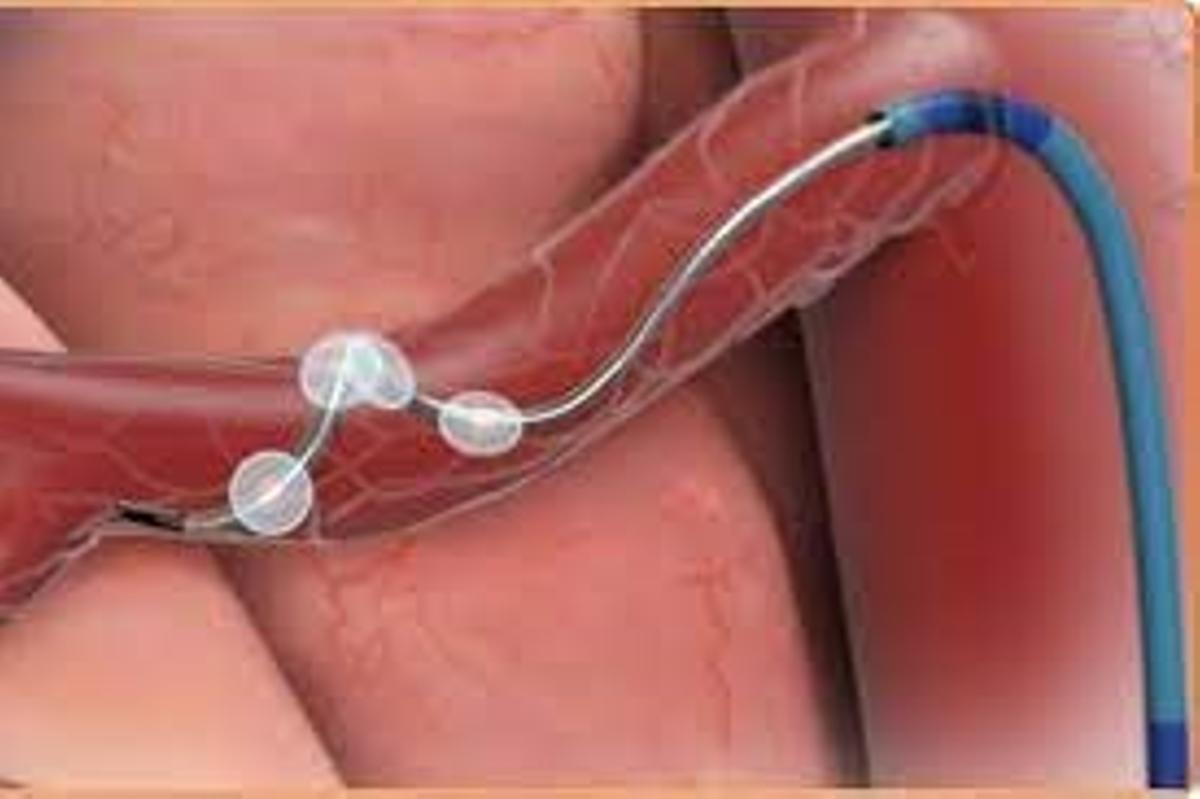

Esta intervención consiste en acceder mediante un catéter, por el interior de una arteria renal, hasta la red de nervios que envuelve el vaso y cuya activación desmedida causa en gran parte la HTA. El catéter lleva 4 electrodos que se posicionan en la pared arterial, emitiendo ondas de radio capaces de inactivar estos nervios, sin efectos secundarios.

La denervación de arterias renales es un procedimiento hemodinámico. El especialista, mediante una punción mínimamente invasiva accede a la arteria femoral, introduciendo un catéter que guía hasta las arterias renales, auxiliado por una angiografía (Rayos X) que permite identificar las arterias diana y actuar sobre el sistema nervioso que las rodea.

«Esta intervención —añade el Dr. Vergara— ha evolucionado tecnológicamente en los últimos años, mejorando su efectividad clínica, pasando de utilizarse un catéter con un único electrodo a otro con cuatro. Esos electrodos transmiten radiofrecuencia generadora de calor a la pared arterial provocando la ablación de los nervios periféricos».

Una punción mínimamente invasiva permite acceder a la arteria femoral. / Juaneda Hospitales